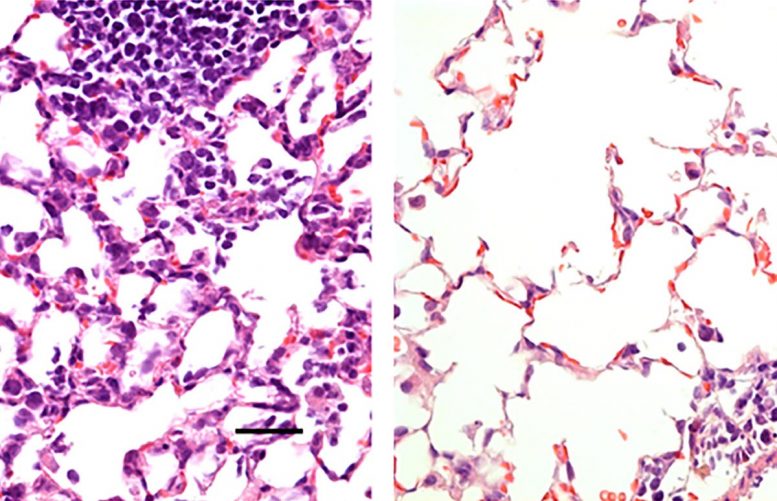

Bên trái là mô phổi của một con chuột được tiêm vaccine đối chứng không tạo ra tác dụng bảo vệ khiến nó bị nhiễm SARS-CoV-2, loại virus gây ra Covid-19. Hình ảnh cho thấy một số lượng lớn các tế bào viêm. Bên phải là mô phổi của một con chuột được nhỏ vaccine Covid-19 mới qua mũi. Vaccine đã bảo vệ chuột chống lại nhiễm trùng, và không có số lượng lớn các tế bào viêm nhiễm. Ảnh: Hassan et al.